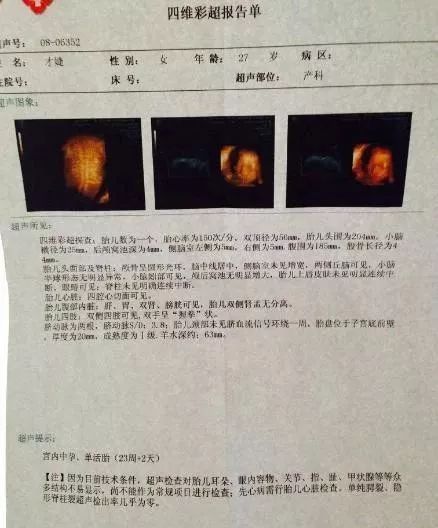

B超探测出来的头像是黑白的,只能探测到宝宝的大概情况,一般在孕早期做B超就够了。彩超探测出来的是彩色图片,可以探测到胎儿的血流情况,能够及时发现胎儿是否异常。四维彩超就像摄影机的VCR,能够及时发现胎儿先天性畸形。

1. 能够更准确的检测出胎儿是否异常,及时发现胎儿的面部、大脑、骨骼等不良情况,以便尽早治疗。

2. 能准确的检查出是否患有先天性畸形。

3. 能清楚得看到在妈妈肚子里时的动态,还能够看到胎儿的面貌,四肢,内脏器官的发育情况。

4. 四维彩超不仅能够检测宝宝的情况,不能看到妈妈子宫的全貌,可以检测到子宫结构是否异常。比如:肿瘤、子宫畸形等。

进行四维彩超时的确是可以判断胎儿性别的,只是按照规定,医生会回避拍摄胎儿的生殖器等性别特征,在后面截图以及制作光盘,都会回避掉可能泄露胎儿性别的部分。